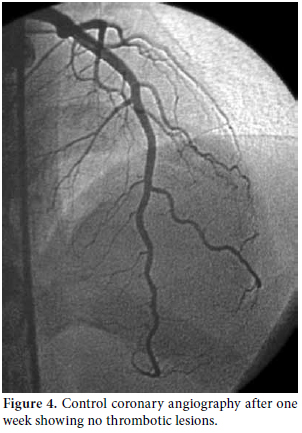

Consultations were then held with the pulmonary medicine and rheumatology departments regarding the eosinophilia identified in the CBC, pulmonary opacities revealed via chest X-ray, and the patient's past history of asthma (Figure 3). Furthermore, cranial computed tomography (CT) was performed on the day after the angiography which showed neurological involvement or paranasal sinus abnormality with a prediagnosis of CSS. The results of the cranial CT were also consistent with chronic sinusitis. The presence of asthma, hypereosinophilia of >10%, chronic sinusitis, and pulmonary opacities represent four of the six ACR criteria required for the diagnosis of CCS.[5] Our patient tested negative for anti-nuclear antibodies (ANAs), anti-double stranded DNA (antidsDNA), extractable nuclear antigens (ENAs) and anti-neutrophil cytoplasmic antibodies (ANCAs). The corticosteroid methylprednisolone at an initial dosage of 80 mg per day (1 mg/kg/d) was prescribed after the termination of the tirofiban infusion. Afterwards, the patient's eosinophil levels in the CBC decreased to normal ranges, and symptomatic relief was completely provided. Control coronary angiography was performed one week later, and the thrombotic lesions had disappeared (Figure 4). In addition, chest radiographs showed complete resolution of the opacities (Figure 5). After two more weeks, control echocardiography was performed revealing a normal morphology of the ventricles without any segmental wall motion abnormalities. Furthermore, the pericardial fluid had also disappeared.